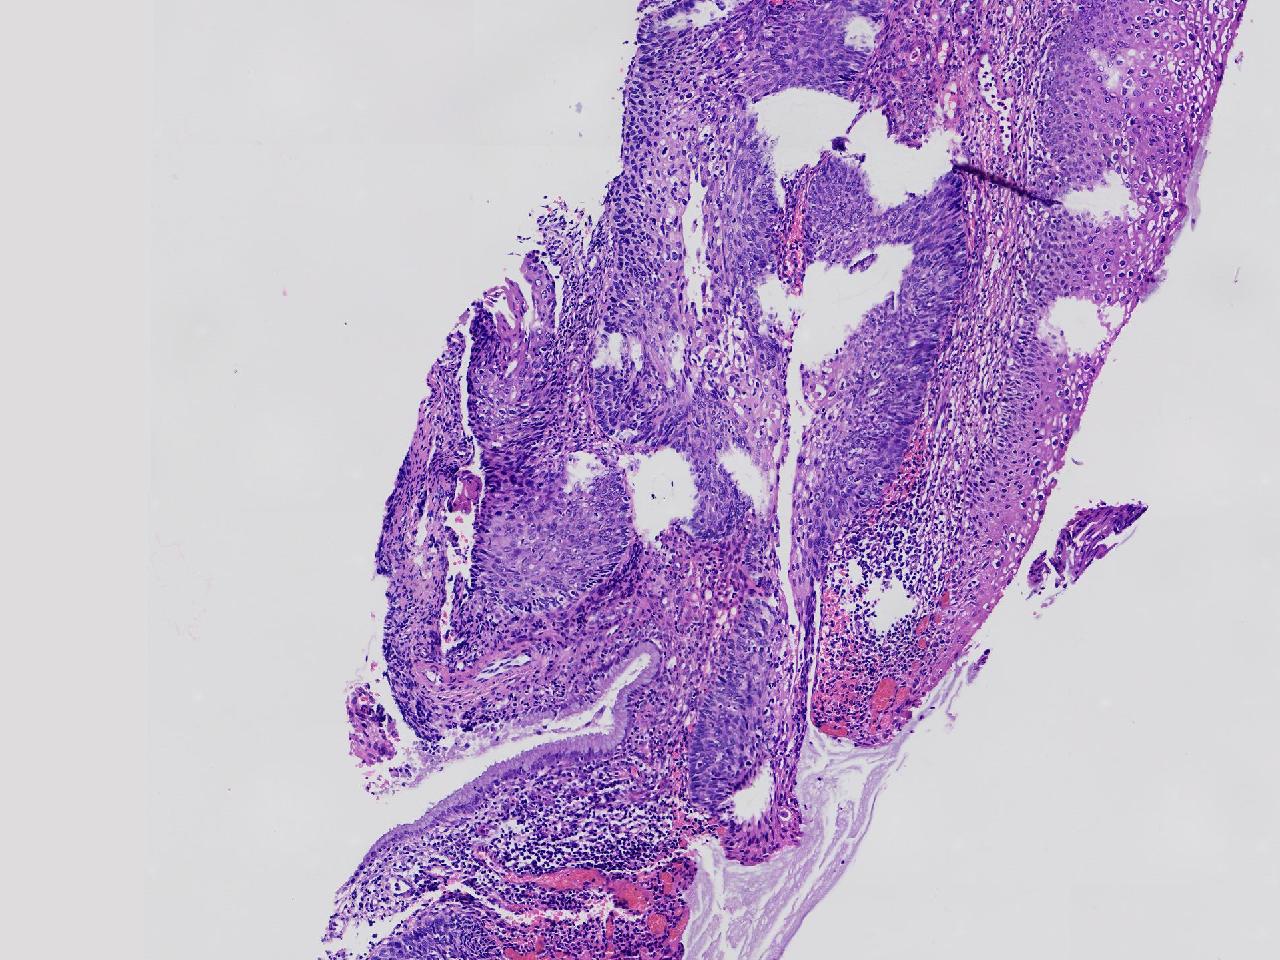

CIN1级? CIN2级?

女,49岁,宫颈11点活检,HPV:16+ 42+

宫颈11点活检。

灰白色不整形软组织1块。

图3

2级

2级,累腺。